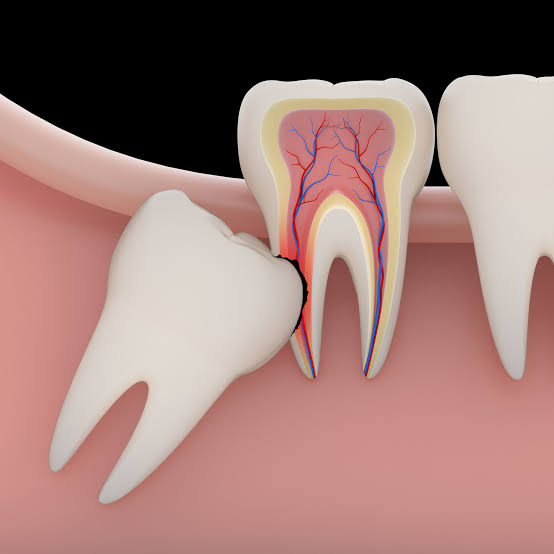

اسباب خلع ضرس العقل

يمكنك استخدام أفضل مسكن بعد خلع ضرس العقل والذي قد يتم خلعه لأسباب متعددة، لعل أبرزها ما يلي:

- نتيجة وجود تسوس في الضرس.

- بسبب وجود بعض الأمراض في اللثة.

- الإصابة بنوع ما من التهابات.

- وجود ورم أو تكيس حميد في ضرس العقل.

- عدم توفر مساحة حتى ينمو ويظهر فيها ضرس العقل.

- من الممكن وجود صديد في المنطقة التي تحيط بضرس العقل.

- في بعض الحالات يخرج ضرس العقل من زاوية غير طبيعية فيمكن أن يظهر في عظم الفك وخروجه يسبب ألم كبير جدًا.

- من الممكن ظهور ضرس العقل تحت اللثة مما يؤدي إلى الحاجة لإجراء عملية جراحية.

أعراض ظهور مشاكل في ضرس العقل

يوجد أعراض عديدة قد تظهر نتيجة حدوث بعض المشكلات في ضرس العقل ومن ذلك ما يلي:

- وجود تورم واحمرار في اللثة والمنطقة التي تحيط بضرس العقل.

- عدم القدرة على فتح الفم بشكل طبيعي.

- وجود ألم شديد في الفكين.

- نزيف وألم ملحوظ في اللثة.

- ظهور ورم في الفك.

- عليك استشارة الطبيب في هذه الحالة، فهو من يستطيع أن يقرر إذا كان يريد الخلع أم أنها حالة عادية ويمكن علاجها بطرق سهلة.

مراحل خلع ضرس العقل

يوجد مراحل وخطوات متعاقبة يتم عن طريقها عملية الخلع، ومن هذه المراحل ما يلي:

- يتم وضع المخدر موضعيًا أو كليًا ويوضع المخدر حسب حالة المريض، وقد يحتاج المريض إلى تناول مسكنات قبل تلك العملية الجراحية.

- عمل أشعة قبل بدء العملية.

- يتم شق اللثة أو إبعادها عن المنطقة المحيطة حتى يظهر ضرس العقل بوضوح، ويتم ذلك إذا كان ضرس العقل مدفون تحت اللثة.

- استخدام أدوات خاصة حتى يعمل على حفر العظام وفصل ضرس العقل، وذلك إذا كان الضرس مدفون في عظم الفك أو أن يكون مغطي بالعظم.

- يعمل الطبيب على قطع الرابط بين الضرس مع اللثة والفك إذا كان الضرس فوق اللثة.

- يخلع الضرس مرة واحدة ومن الممكن أن يقطع ضرس العقل لكي يتم تسهيل خروجه.

- يستخدم أدوات خاصة حتى يسهل خلعه من اللثة.

- يعمل الطبيب في عملية خلع ضرس العقل على تقطيب اللثة مكان الخلع تبعًا للحالة.

- ثم يضع قطعة من القطن على مكان الجرح ويطلب الطبيب من المريض أن يثبتها بفكه جيدًا لمدة ساعة بعد إجراء العملية الجراحية حتى يتخثر الدم ويقف نزيف الجرح، كما يتم وصف أفضل مسكن بعد الخلع من خلال الطبيب عقب إتمام تلك الجراحة.